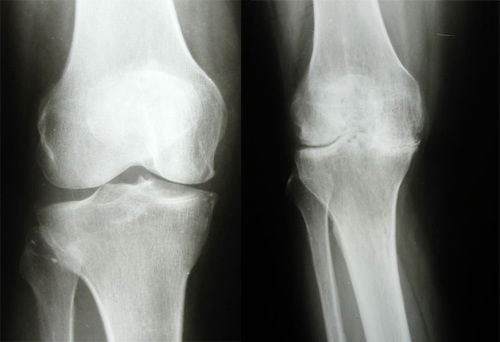

Хвороба, пов'язана з дегенеративними змінами (зношенням) хрящової тканини, яка покриває суглобні поверхні кісток і забезпечує вільні рухи кінцівок.

Якщо вже виявлені виражені дефекти хрящової тканини – консервативна терапія безсильна і для лікування артрозу колінного суглоба необхідна операція. У окремих випадках цикл розвитку патології від перших ознак до тяжкої інвалідності може зайняти всього декілька років.

При гонартрозі операція артроскопії здатна радикально позбавити пацієнта від болю в колі та відновити функцію ураженої кінцівки. Справа в тому, що вже при першій-другій стадіях захворювання на медіальному (внутрішньому) меніску виникають грубі зміни внутрішньосудинної тканини.